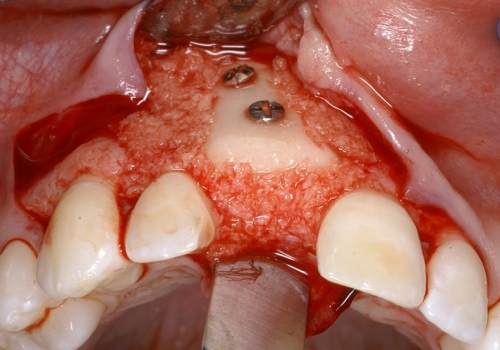

Bərpa texnikasının müəyyən edilməsi, sümüyün hansı bölgədə, hansı miqdarda itirilmiş olmasına bağlı olaraq müəyyənləşdirilir. Bərpa üçün tətbiq edilən sümük materialları pasiyentin öz donor bölgələrindən xüsusi metodlarla qazanılmış sümüklər, o cümlədən digər fərdlərdən alınmış və xüsusi qaydada hazırlanmış materiallar, heyvan mənşəli sümükəvəzləyici materiallar və sintetik materiallar olaraq ayrılır.

Bərpa zamanı yerinə görə bu materiallar ya ayrı-ayrılıqda, ya da kombinə olunmuş şəkildə tətbiq oluna bilir. Gündəlik təcrübədə həmçinin pasiyentdən götürülmüş qan nümunələrindən alınmış yüksək bərpaedici xassəyə malik materiallar (PRF) da uğurla tətbiq olunur. Sümükartırma metodlarının tətbiqi sayəsində, çənədə implantların yerləşdirilməsi üçün yetərsiz sümük həcmi olan bölgələrdə sümük miqdarı yetərli duruma gətirilir, uyğun boy və diametrə uyğun implantlar uğurla tətbiq olunur.